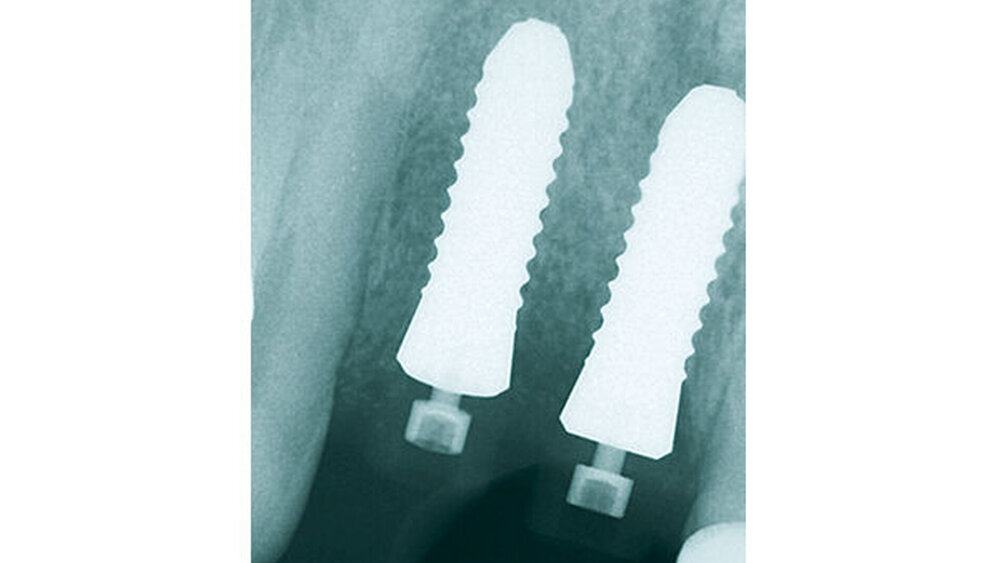

Geplant wurden zwei zweiteilige Hexalobe-Implantate mit dem Durchmesser von 4,0 mm, Länge 12 mm. Die Implantate sollten mit begleitender GBR inseriert werden und anschließend gedeckt einheilen. Das setzte die Wahl eines zweiteiligen Keramikimplantats voraus. Im Vorfeld des chirurgischen Eingriffs wurde eine Mess- und Bohrschablone konventionell nach prothetischem Wax-up für die prothetisch orientierte Implantatinsertion angefertigt.

Mithilfe der Bohrschablone erfolgte die Primärbohrung (Abb. 4). Über eine langsame, niedertourige Implantatbettaufbereitung wurde autologer Knochen für die begleitende GBR gewonnen. Anschließend wurden die beiden CERALOG Hexalobe-Implantate leicht palatinal inseriert. Da Zirkoniumdioxid im Vergleich zu Titan eine geringere Wärmeleitfähigkeit besitzt, sollten die Implantate langsam mit maximal 15 U/min eingedreht werden, um thermische Nekrosen zu vermeiden.

Die Implantatschulter wurde leicht supracrestal platziert, sodass die prothetische Plattform zirka 2 mm unter dem Weichgewebeniveau zu liegen kam (Abb. 5). Lateral der Implantatschulter wurden die autologen Knochenspäne gemischt mit feinkörnigem BioOss (Geistlich) eingebracht und die Implantate über den Klickmechanismus in der Innenkonfiguration des Implantats mit der PEEK-Abdeckkappe verschlossen (Abb. 6). Die CERALOG Hexalobe-Implantate sind im Halsbereich weniger rau als im enossalen Bereich, damit sich das Weichgewebe im Bereich des Implantathalses und die Knochenzellen an der mikrorauen Struktur im enossalen Bereich optimal anlagern können. Das Augmentat wurde mit einer Bio-Gide-Membran (Geistlich) abgedeckt. Es lag ausreichend keratinisierte Gingiva vor, sodass keine Weichgewebeverdickung erforderlich war. Der Wundverschluss erfolgte ohne Periostschlitzung (Abb. 7), um die Ernährungsphysiologie des Weichgewebes nicht zu verschlechtern und eine Verschiebung der Mukogingivalgrenzlinie nach koronal zu vermeiden. Der Lappen ließ sich für den spannungsfreien Wundverschluss tunnelierend ausreichend weit nach subnasal präparieren. Im Anschluss an die Implantatinsertion wurde die Valplast-Prothese basal ausgeschliffen, um augmentationsbedingte Druckstellen zu vermeiden. Die postoperative Röntgenkontrolle (Abb. 8) zeigt eine anatomisch exakte Implantatpositionierung nach Schablonenvorgabe.